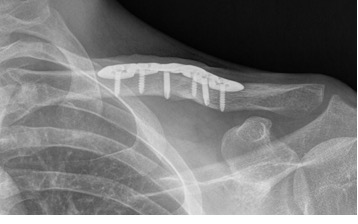

Slechts in bepaalde gevallen is er een reden voor een operatie. Een harde reden voor een operatie kan zijn dat een botstuk door de huid dreigt heen te gaan. Ook kan een sterk afwijkende stand een reden zijn voor een operatie. De nadelen van een operatie (ontsierend litteken, infectiekans, uitbreken van fixatiemateriaal) wegen echter vaak niet op tegen de voordelen (standscorrectie). Uw behandelend arts zal samen met u een afweging kunnen maken hoe dat in uw specifieke situatie is. Bij sleutelbeen breuken waarbij de breuk helemaal aan de zijkant ligt, zal er wel sneller naar een operatieve behandeling worden geneigd. Indien er voor een operatie wordt gekozen, zal er meestal gebruik worden gemaakt van een plaatje met schroeven.